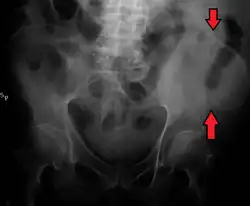

A fracture of the left iliac wing

The iliac crest has a large amount of red bone marrow, and thus it is the site of bone marrow harvests (from both sides) to collect the stem cells used in bone marrow transplantation. The iliac crest is also considered the best donor site for bone grafting when a large quantity of bone is needed. For example, oral and maxillofacial surgeons will often use iliac crest bone to fill in large osseous defects of the oral cavity caused by severe periodontal disease, excess bone resorption following tooth loss, trauma, or congenital defects including alveolar clefts.[4]